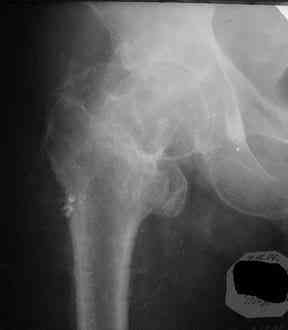

Все-таки хочу поделиться раз затронулась тема, может кому-нибудь и сгодиться. Это пример из области скорее трудноудаляемой. Пациент 50 лет, травма (низкоэнергетическая) 1,5 года назад. Оперирован через неделю (винт отечественный). Через 4 месяца выполнен контрольный снимок, сразу же возник вопрос: почему винт не телескопировался? Вопрос в общем-то так и остался без ответа.

При удалении (наркоз) после неимоверных усилий пришлось выкрутить фиксатор единым блоком и только тут все встало на свои места. См. фото.